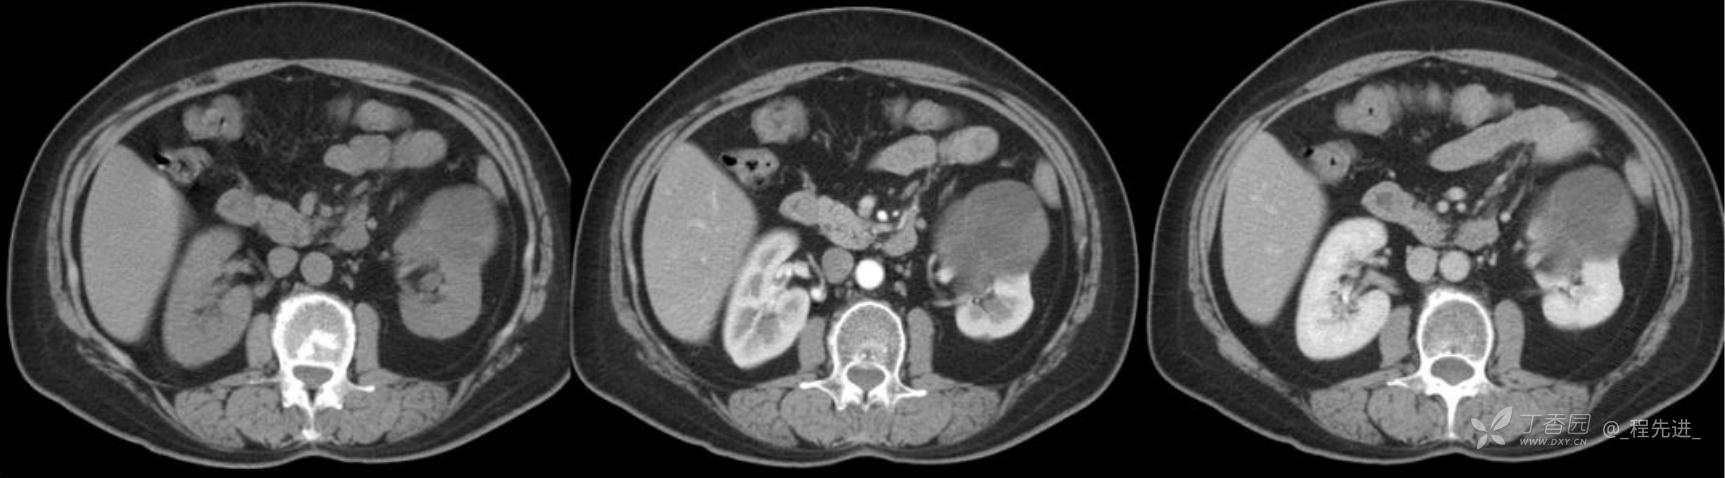

左肾罕见肿瘤病例一例

患者性别:女

患者年龄:53岁

简要病史:反复头昏、头痛5年,再发加重3月

辅助检查:无特殊,输血前检查、生化检查均正常

混合性上皮和间质肿瘤 (1)